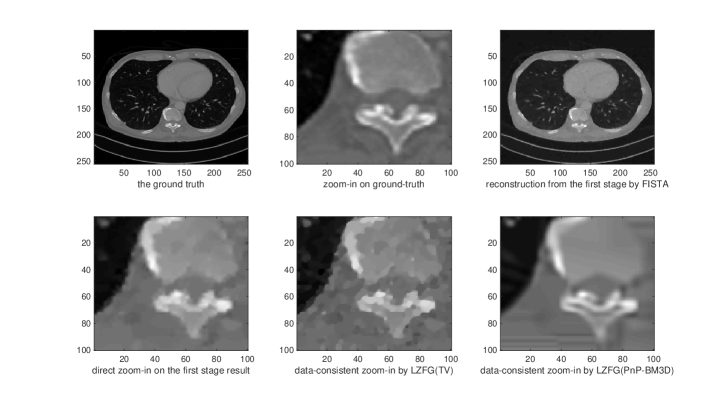

As we can observe, the reconstructed image has a reasonable quality, but could oversmooth some of the local areas which may need to be refined and zoomed in. This observartion suggest that although the regularization can be optimized to provide the best PSNR globally, classical iterative methods indeed have such a limitation for not taking care of local reconstruction performance. In this example we seek to zoom-in 4 times larger a by block of a by first-stage image. Hence the global iterative superresolution of the whole image will be 25 times more expensive than our approach in this setting. Direct zoom-in on this block would often have poor performance since it does not re-utilize the measurement data. We then test two instants of our LZFG framework. For the first one we use TV regularization while for the second one we use BM3D denoiser (Dabov et al., 2007). We use the MATLAB imresize function as the up-sampling and down-sampling operators, with the default bicubic interpolation.

We present in Figure 2, 3, 4, and 5 four examples of local zoom-in. We can observe from the numerical results that our method can indeed recover the details of the local blocks with high-quality. The direct zoom-in from the first-stage reconstruction fails to recover local details missed from the first-stage reconstruction since it does not utilize the measurement data, demonstrating the importance of data-consistency in local zoom-in of medical images. We present the convergence curves of LZFG with TV and BM3D in Figure 1 reporting the PSNR results towards the zoomed-in ground-truth image. From the PSNR result we can observe that our methods provide significantly improved reconstruction accuracy (5 to 10 dB better) compared to the naive approach.